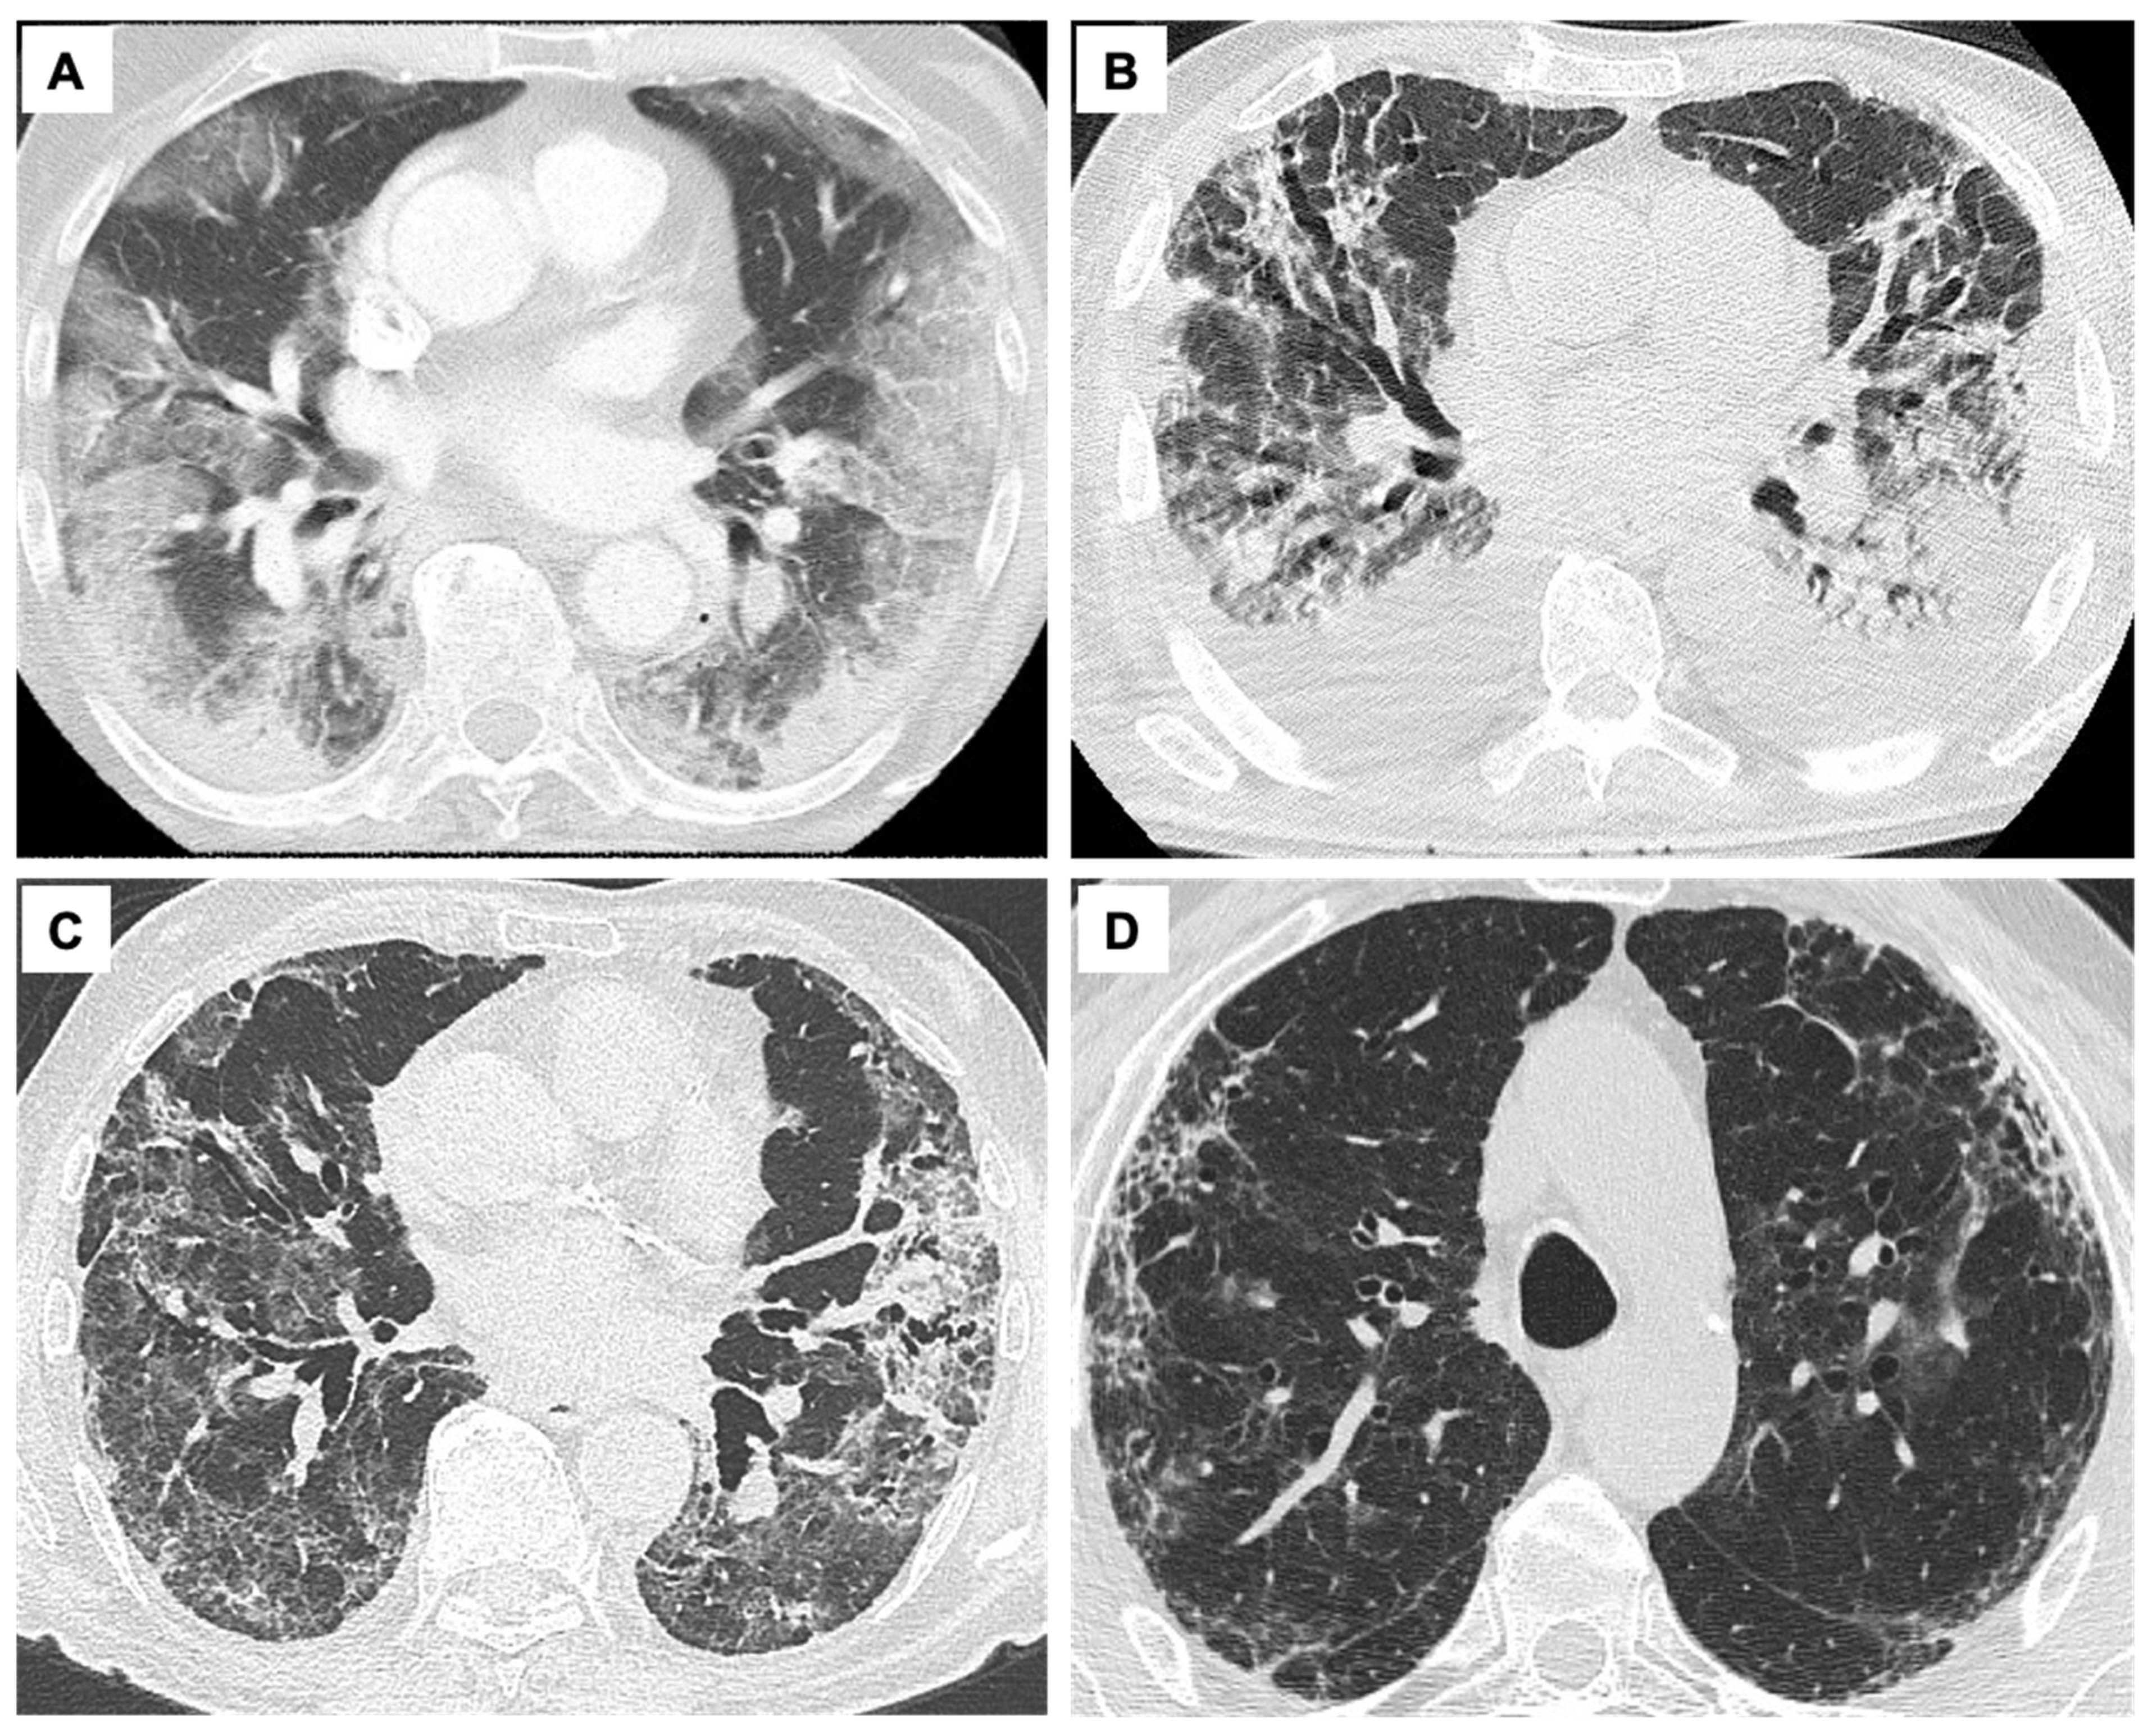

| COVID-19 ARDS | Phenotype 1 | Alveolar collapse and rupture Intra-alveolar hemorrhage Hyaline tissue formation (rare) Microthrombi, vasculitis or vascular thrombosis Polymorphonuclear and monocytes infiltration (initial) SARS-CoV-2 replication in type II pneumocytes Reactive pneumocytes with nuclear atypia and hyperplasia Mallory like intracytoplasmic inclusions in type II pneumocytes Masson’s bodies | Multiple focal over perfused ground glass opacities and normally aerated areas Possible diversion of ventilation toward non-dependent aerated lung regions and reduction in pulmonary perfusion due to increased airway pressure Collapse of capillaries and/or micro-thrombosis and formation of no recruitable atelectasis | Clinical manifestation Normal compliance of the respiratory system Hypoxia (increased areas with altered V/Q ratio) Suggested treatment NIRS (HFNC, CPAP, NIV) with high FiO2 and respiratory monitoring (i.e., clinical deterioration, gas exchange, FOT, esophageal manometry) IMV when NIRS failed (using lower PEEP) |

| Phenotype 2 | Alveolar collapse and rupture Intra-alveolar hemorrhage Hyaline tissue formation (prevalent) Microthrombi, vasculitis or vascular thrombosis Early fibroblastic interstitial fibrosis, septal and para-septal reparative fibrosis Polymorphonuclear and monocytes infiltration (prevalent) Reactive pneumocytes with nuclear atypia and hyperplasia Mallory like intracytoplasmic inclusions in type II pneumocytes Masson’s bodies | Patchy ARDS-like pattern Inhomogeneously distributed and hyper/hypo-perfused areas Increased lung weight and consolidated Non-aerated lung regions (dependent lung regions) | Clinical manifestations Decrease of aerated lung regions Impairment of compliance of the respiratory system Increased shunt (blood flow redistribution to injured areas with hypoxic vasoconstriction, thrombosis, and compression of capillaries) Suggested treatment IMV (low VT 4–6 mL/kg PBW, higher PEEP to redistribute ventilation and perfusion, Prone positioning (partial redistribution from dorsal to ventral areas, no effective recruitment) | |

| Phenotype 3/F | Hyaline membranes Fibroblastic interstitial fibrosis, septal and para-septal reparative fibrosis (prevalent) Parenchymal bands, irregular interfaces, reticular opacities Traction bronchiectasis with or without honeycombing | Final evolution to fibrosis Possible traction bronchiectasis and reticulation | Clinical manifestations Low diffusing capacity for carbon monoxide (DLCO), altered gas exchange Suggested treatment Symptomatic treatment (i.e., oxygen, corticosteroids, antifibrotic drugs like nintedanib, antibiotics, etc.) | |